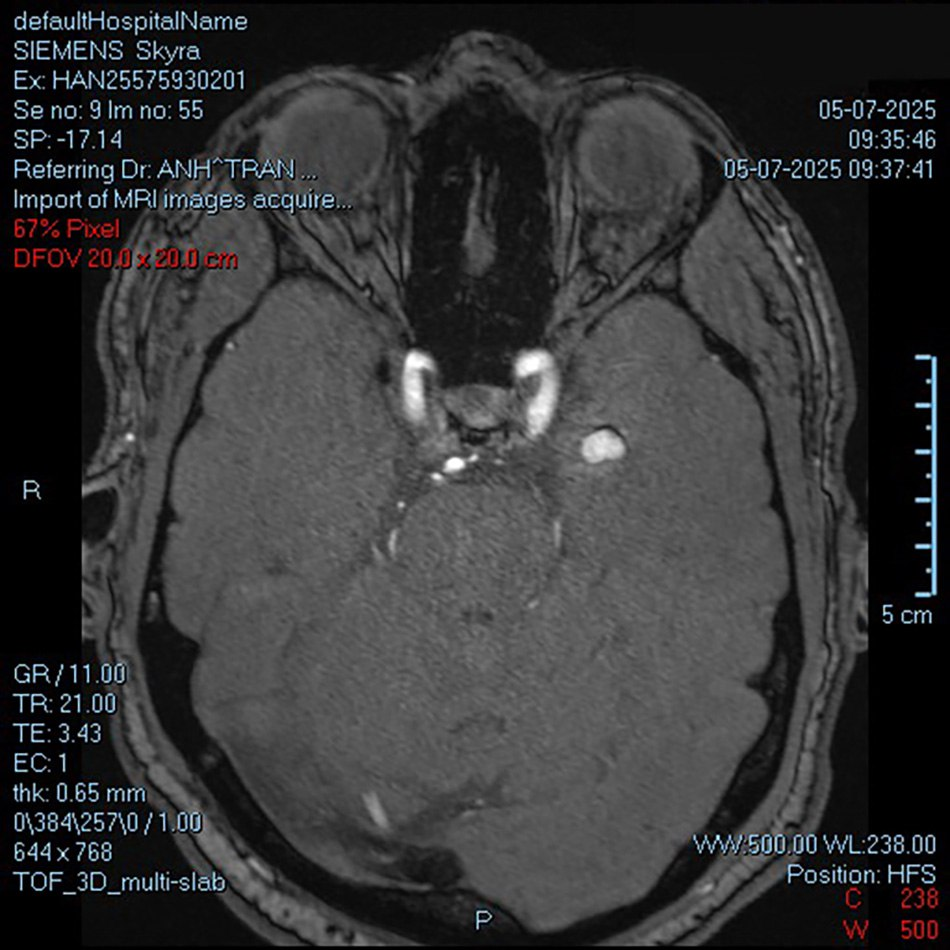

ថ្មីៗនេះ លោក S.F. អាយុ ៦៣ឆ្នាំ សញ្ជាតិអូស្ត្រាលី កំពុងប្រឈមនឹងការឈឺទ្រូងធ្ងន់ធ្ងរ។ ដំបូង គាត់ បាន ទៅ មន្ទីរពេទ្យ ឯកជន ធំ មួយ ដើម្បី ពិនិត្យ។ លទ្ធផលតេស្តសរសៃឈាមបេះដូងគឺធម្មតាទាំងស្រុង ប៉ុន្តែនៅពេលថតបន្ថែម MRI ខួរក្បាល គ្រូពេទ្យបានរកឃើញដុំសាច់តូចមួយ ហើយធ្វើរោគវិនិច្ឆ័យថាការឈឺទ្រូងអាចជាការបង្ហាញដែលបណ្តាលមកពីជំងឺឆ្គួតជ្រូក។

វេជ្ជបណ្ឌិតឯកទេស២ ត្រឹងលឿងអាញ់ ប្រធានផ្នែកវះកាត់សរសៃប្រសាទ និងឆ្អឹងខ្នង បានពីពិនិត្យ និងវិភាគលទ្ធផល ដោយបានរកឃើញថា អ្នកជំងឺមានដុំសាច់សរសៃឈាមក្នុងប្រហោងដ៏កម្រ ដែលមានទីតាំងនៅ hippocampus ក្នុងតំបន់កំពកសៀតផ្កា តំបន់គ្រប់គ្រងមុខងារនៃការចងចាំរហ័ស។

«នេះគឺជាដុំសាច់សរសៃឈាមពីកំណើត ដែលជាធម្មតាបង្ហាញរោគសញ្ញានៅពេលដែលមានការហូរឈាម ឬនៅពេលដែលវាមានទំហំធំ។ ដោយសារតែវាស្ថិតនៅទីតាំងសំខាន់មួយនៅក្នុងខួរក្បាល នៅពេលដែលវាហូរឈាម ដុំសាច់នឹងបង្កការប្រកាច់» លោកវេជ្ជបណ្ឌិត លឿងអាញ់ បានពន្យល់។

ដុំសាច់នេះទោះបីមានទំហំត្រឹមតែ 9x14mm ក៏ដោយ ប៉ុន្តែត្រូវបាន «លាក់»ជម្រៅ ៥cm នៅក្នុងស្រោមខួរក្បាល ដែលជាទីតាំងរសើបបំផុត។